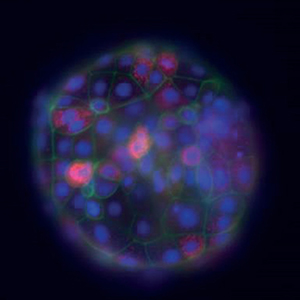

I försöken visade det sig att färre embryon utvecklades normalt då äggen hade mognat vid en förhöjd insulinnivå. Dessutom fick embryona ett annorlunda utseende. Cellstrukturer som är kopplade till energiomsättning (mitokondrier) och cellstabilitet (aktin) var förändrade, och insulinbehandlade embryon hade fler celler – de hade alltså vuxit snabbare.

Koembryo, dag 8 i utvecklingen, som färgats för att tydliggöra olika strukturer. Grönt visar cellskelettet (aktin), blått visar cellkärnor (DNA) och orange visar mitokondrier. Foto: Denise Laskowski